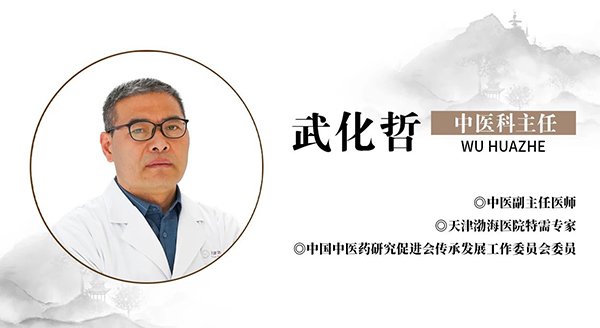

今天我们邀请到中国中医药研究促进会传承发展工作委员会委员,天津渤海医院特需专家,中医杂病专家武化哲主任与大家来聊一聊肺炎。

名医简介

专家介绍

从事临床工作近30年,熟读经典,博览群书,曾跟随国医大师唐祖宣学习,对其用益气活血法治疗脉管炎颇有心得。在国家级期刊发表论文10余篇,善于运用体质辨证及六经辨证进行辨证论治。拥有丰富的临床经验,秉承传统中医理论,运用中西医结合方法诊疗受到了良好效果。

专家擅长

擅长经方治疗鼻炎,哮喘,支气管炎,急慢性胆囊炎,胆结石,慢性胃炎,胃溃疡,十二指肠溃疡,结肠炎,痤疮,湿疹,银屑病,高血压,冠心病,泌尿系结石,前列腺炎,肺结节,甲状腺结节。擅长运用已故名老中医李可老先生的“攻癌夺命汤”化裁加减治疗肿瘤:恶性淋巴瘤,胃癌,食道癌,肝癌,甲状腺癌,骨瘤,宫颈癌,肾癌,膀胱癌等。不仅可以有效提高患者生活质量,还可延长患者生存时间!